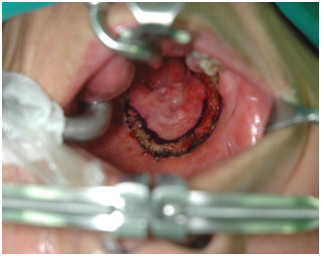

방사선 치료를 받은 환자들은 구강 및 구인두 내에 특징적으로 점막염(mucositis)을 일으킵니다. 점막염은 보통 점액의 양과 성질을 변화시켜 장기적으로 건조감을 일으킵니다. 보통은 국소치료로 잘 조절되나, 때로는 이러한 점막염이 심해져 섬유화를 일으키면 연하장애를 유발할 수 있으며, 이것이 환자의 체중감소를 일으켜 결과적으로 수술 전후의 상처회복에 나쁜 영향을 줄 수 있습니다. 미각변화도 올 수 있습니다. 방사선치료 후에 종양부위와 목에 섬유화가 일어나면 환자에게 불편함을 줄 뿐 아니라 목의 경직을 일으켜서 오랫동안 내부에 있는 종양을 놓칠 수 있습니다. 목의 경직이 오면 목의 운동장애를 일으키므로 집중적인 물리치료가 필요할 수도 있습니다.

[점막염(mucositis)]